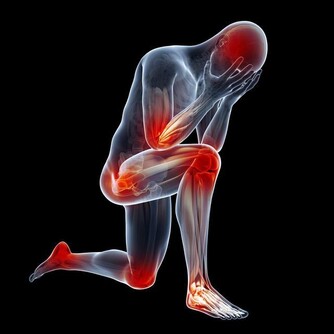

21. 癌症風險高

關於睡眠與癌症之間的關聯,

目前的研究仍在初期階段,不過就目前的結果來看,

睡眠不足確實會增加罹癌的風險,特別是大腸癌與乳癌。